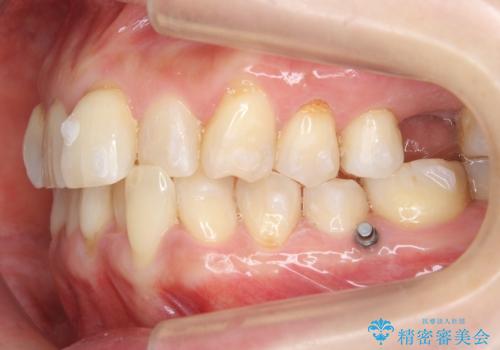

事前にワイヤーによる部分矯正を行い、矯正用ミニスクリューを植立しています。

右上大臼歯2本の欠損については、インプラント治療をお勧めしましたが、ご希望によりそのままとなりました。